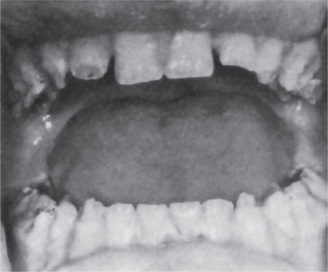

It is well established that vitamin A is concerned primarily with the process of differentiation of epithelial cells. In vitamin A deficiency the epithelial cells fail to differentiate. This means that the cells in the basal layer lose their specificity and tend to form a stratified squamous epithelium with keratin production, independent of the type of cell previously formed by the basal cells. Thus one of the basic changes is a keratinizing metaplasia of epithelial cells. This occurs throughout the body, including the mucous membranes of the trachea, conjunctiva, and ureter, and the salivary and other glands (Fig. 15-7).

Figure 15-7 Vitamin A deficiency.

Photomicrographs of the tongue of a normal rat (A) and of vitamin A-deficient rat (B, C). There is squamous metaplasia in the mucous glands of the tongue and a large cyst filled with keratinaceous material (B).